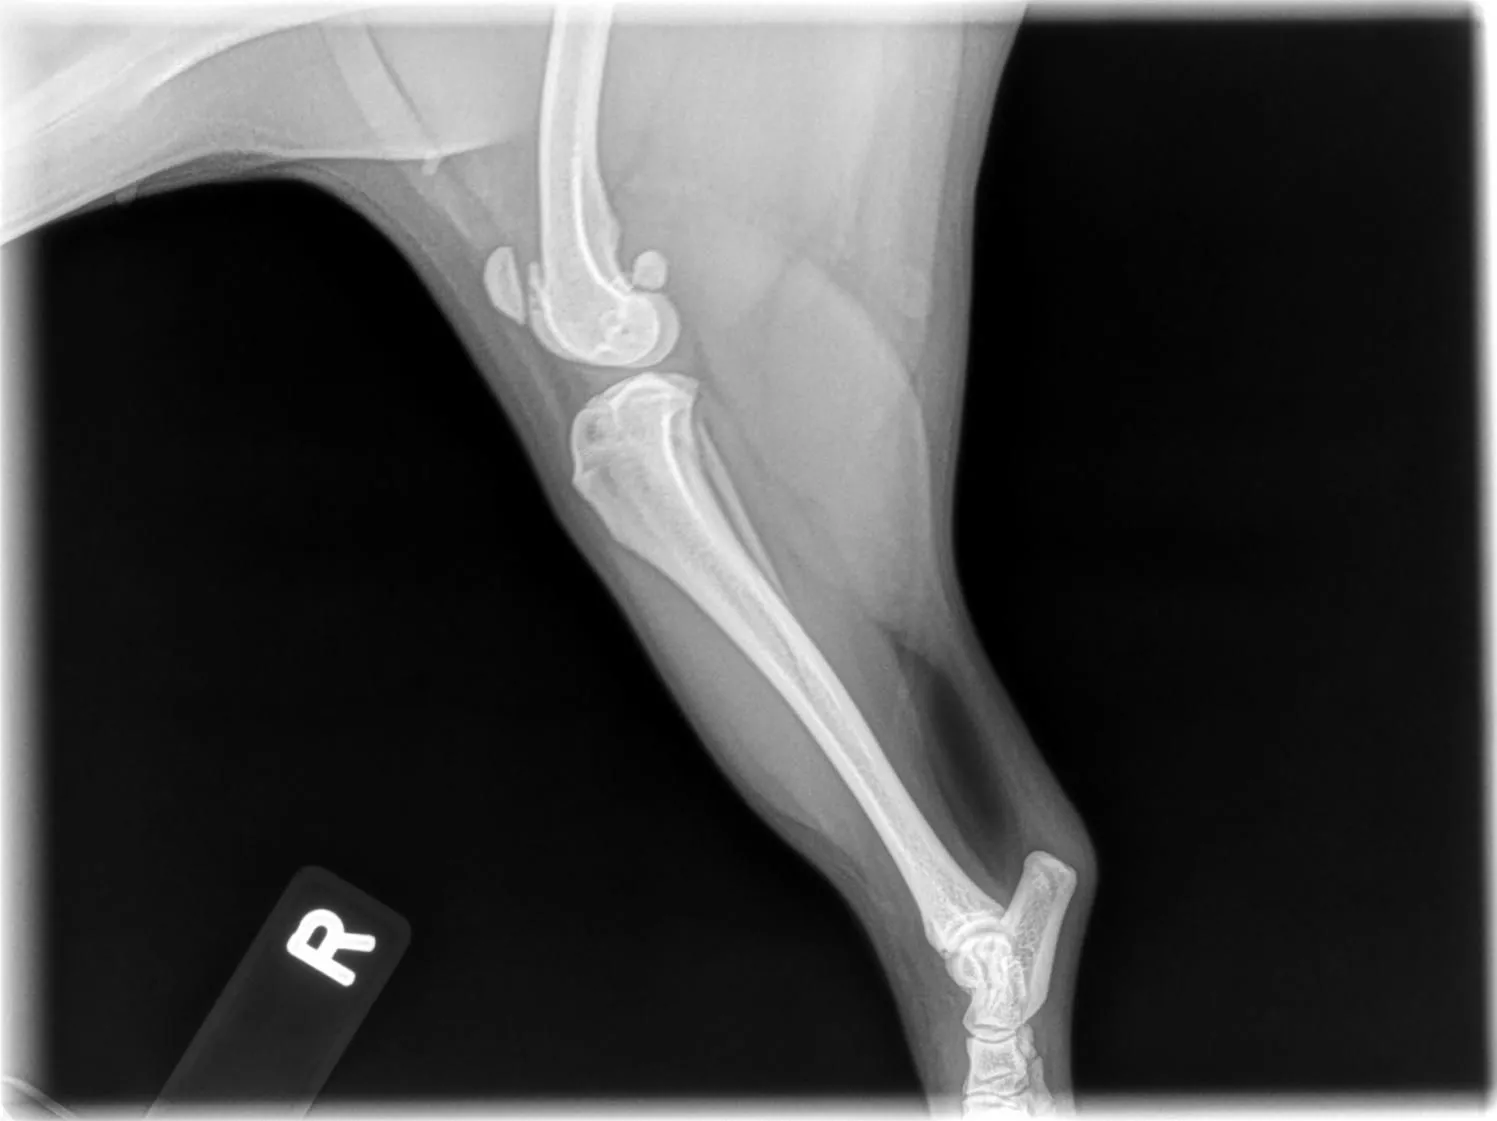

Here are the x-rays that i received from the vet. Not sure if anyone on here can look at them and see what is going on.